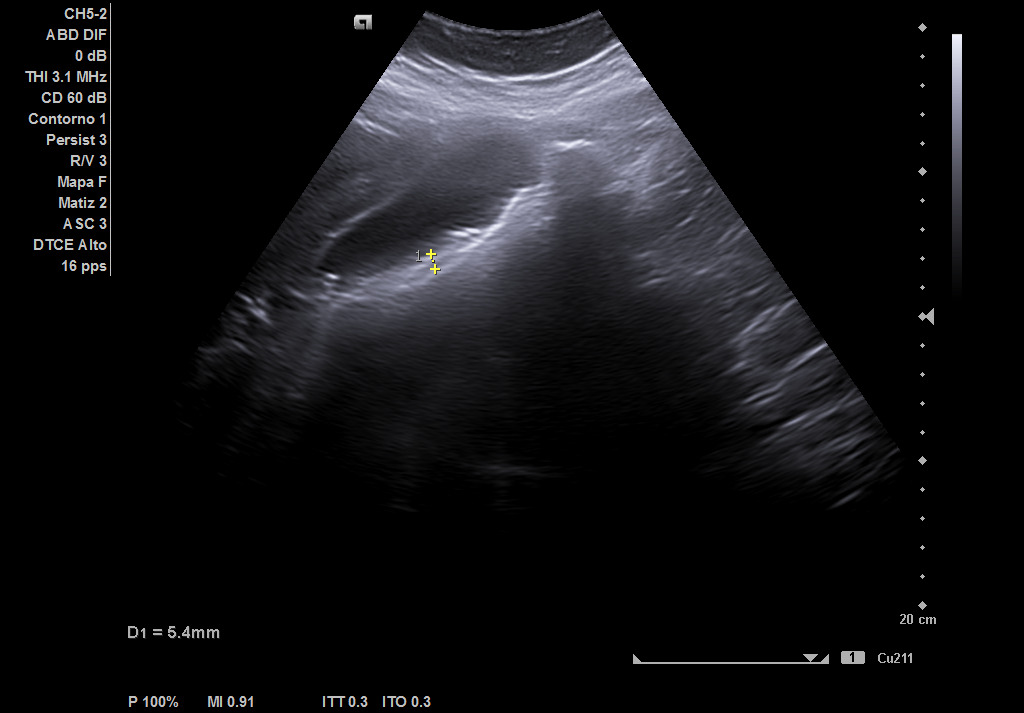

Hígado de tamaño, forma y ecoestructura conservadas, con parénquima homogéneo. Vena porta de calibre conservado. Colédoco dilatado, de 8,8 mm. Vesícula biliar de paredes gruesas y edematizadas (5,4 mm) en cara posterior, con contenido ecogénico y 2 microlitiasis en su infundíbulo.